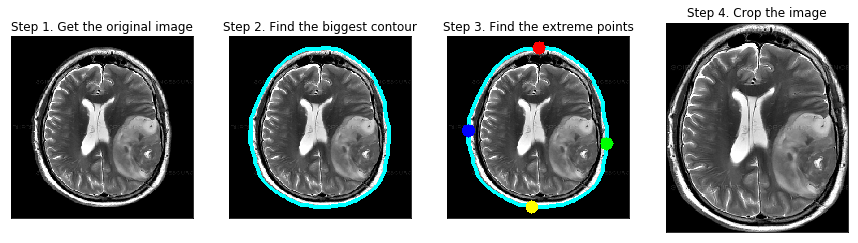

削除の流れとしては、下記にあるように4ステップで進めていきます(Step1は読み込むだけなので処理としては3ステップ)。

やってることとしては、まずはSTEP2で画像の輪郭を取得します。

この時、RGBだと輪郭が取り辛いので一旦グレースケールに変換しています。

ここでは0〜255諧調のうちの45で区切ってますが、どこで白・黒を区切るかはさじ加減ですね。

STEP3では、その輪郭から一番外側のポイントを4つ取得しています。

最後のSTEP4では、その4つのポイントを通る四角形を作り、それ以外の部分を削除することで脳の画像だけが残るようにしています。